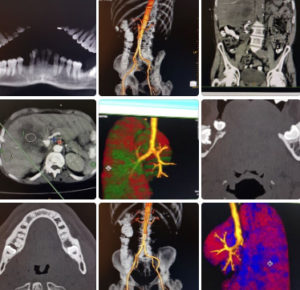

SALUD: Suman prestaciones a los tomógrafos de los hospitales rionegrinos

Los cuatro hospitales de mayor complejidad de la provincia experimentaron una transformación fundamental en los últimos años en el diagnóstico…